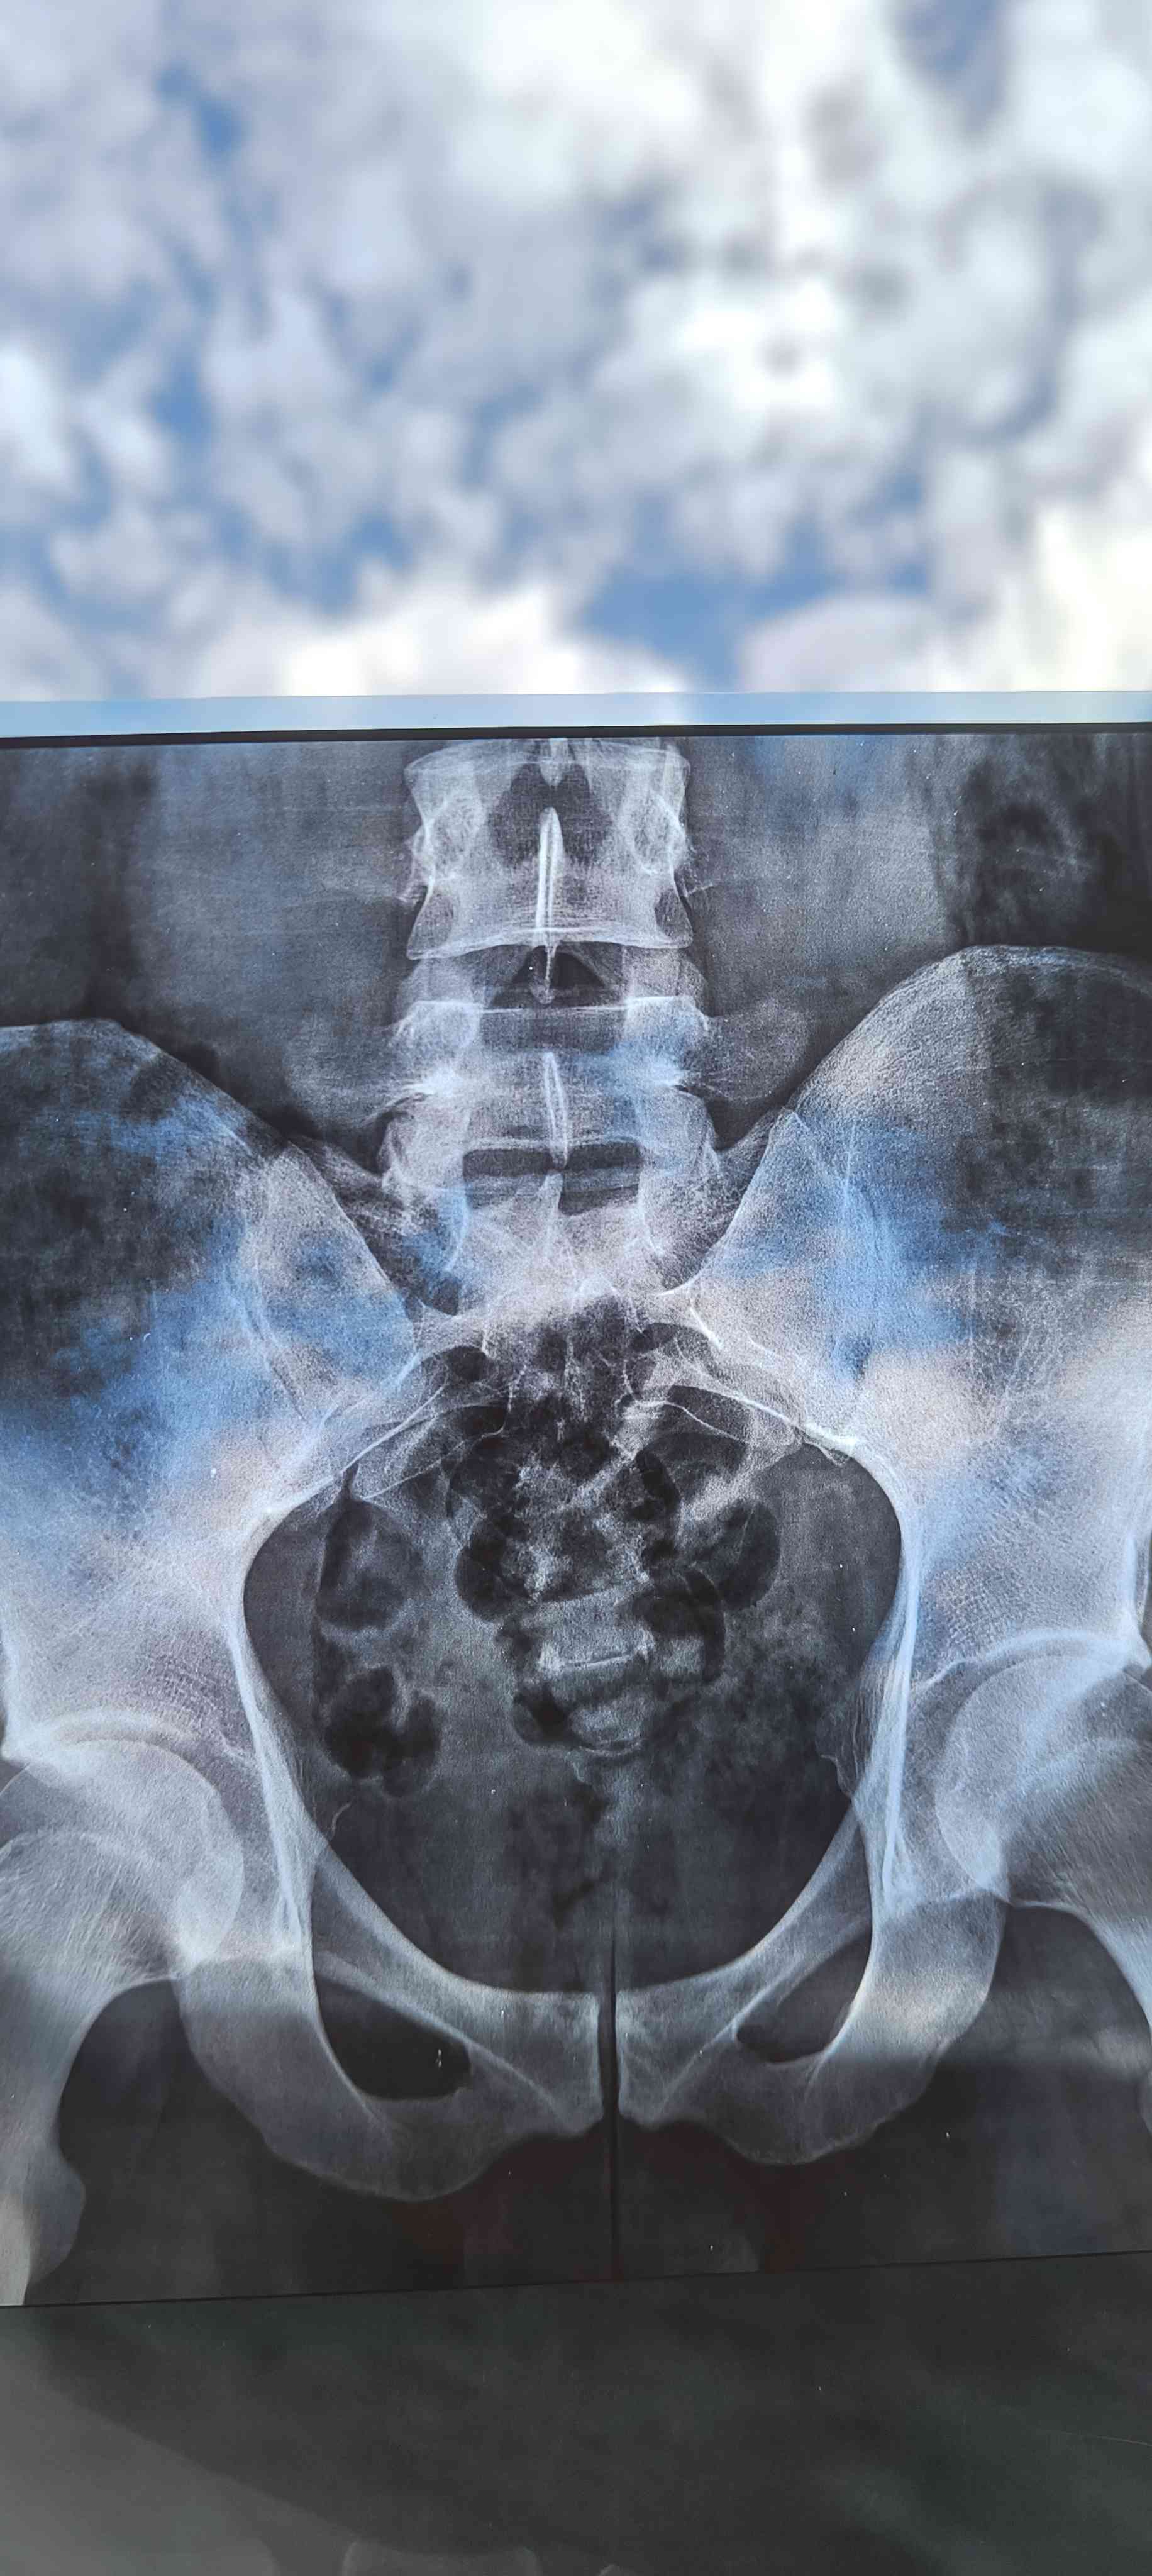

هل حالتي تاكل غضروف الفقرة L5 S1 بتتعالج لدي ألم جانب اليمين في الورك يمتد لأسفل الساق وأسفل الظهر

هذه لاتكفي للتشخيص وممكن تحتاج لرنين --الفحص السريري مهم عليك مراجعة طبيب روماتيزم لاجراء اللازم من تصوير وتحليل للدم مثلا CBC ESR CRP ومعرفة وظائف الاعضاء واليك بعض من النصائح الطبيبه في حياتك اليوميه -وساده سمكها 8-12 سم صلبه نوعا ما والحذر عند استخدام الجوال عدم الانحناء عدم رفع الاشياء الثقيله والنوم والجلوس الصحي والوقوف يكون بتباعد القدمين او رفع احدهم على مرتفع كلوح او طوبه الخ وعند تناول اي جسم يكون بثني الركبتين وممكن العلاج الطبيعي حسب ما يراه 1 2026-03-28T07:42:50+00:00 2026-03-28T07:42:50+00:00

هذه لاتكفي للتشخيص وممكن تحتاج لرنين --الفحص السريري مهم عليك مراجعة طبيب روماتيزم لاجراء اللازم من تصوير وتحليل للدم مثلا CBC ESR CRP ومعرفة وظائف الاعضاء واليك بعض من النصائح الطبيبه في حياتك اليوميه -وساده سمكها 8-12 سم صلبه نوعا ما والحذر عند استخدام الجوال عدم الانحناء عدم رفع الاشياء الثقيله والنوم والجلوس الصحي والوقوف يكون بتباعد القدمين او رفع احدهم على مرتفع كلوح او طوبه الخ وعند تناول اي جسم يكون بثني الركبتين وممكن العلاج الطبيعي حسب ما يراه